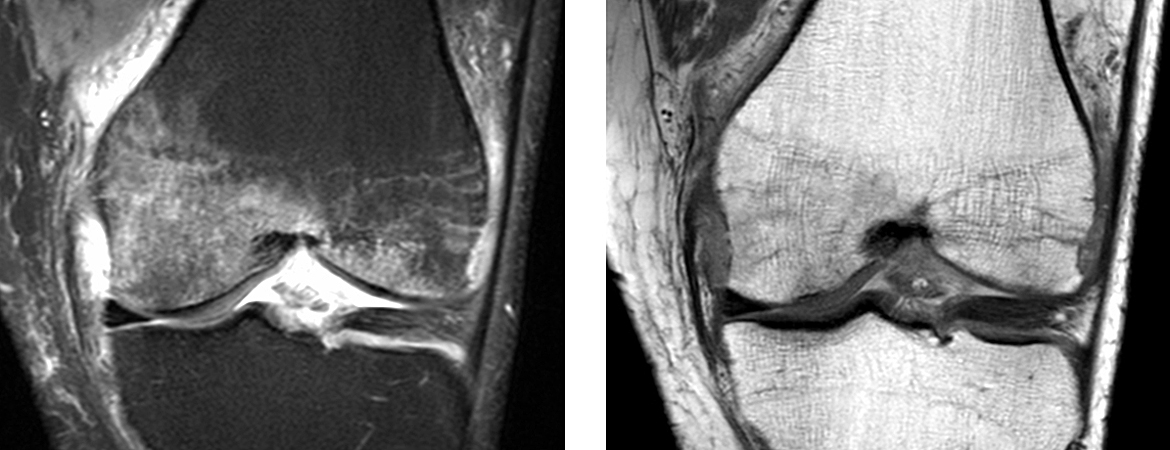

Livia Küchler, Thomas Fehr, Raphael Jeker (Author) Pain control with ibandronate for bone marrow oedema of the knee Fulltext PDF Fulltext HTML Appendix